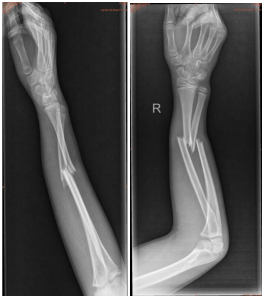

我科典型病例:

5岁男童,尺桡骨双骨折

术后